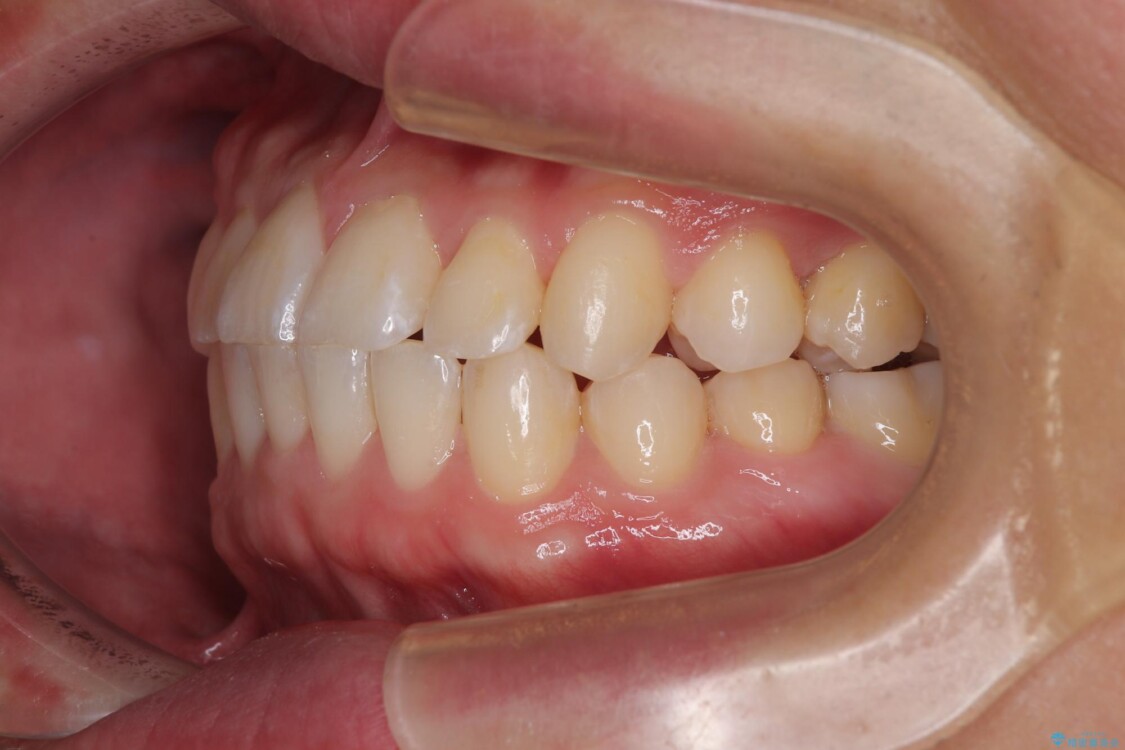

主訴:前歯のデコボコと奥歯のかみ合わせを治したい 今回ご紹介するのは、「前歯のガタガタ(叢生)」と「奥歯のかみ合わせ(シザーズバイト)」にお悩みでご来院された患者様の症例です。 患者様は、 ・歯並びをできるだけ早く改善したい ・費用を抑えた矯正治療 というご要望をお持ちでした。

・上顎左右の第二大臼歯が頬側へ転移し、シザーズバイト(scissors bite)の状態

・上顎左側第二小臼歯が90度捻転しており、噛み合わせに影響

治療前

• 前歯のガタガタ・奥歯のかみ合わせ(シザーズバイト)を改善|1年半で完了したメタルブラケット矯正 治療前画像